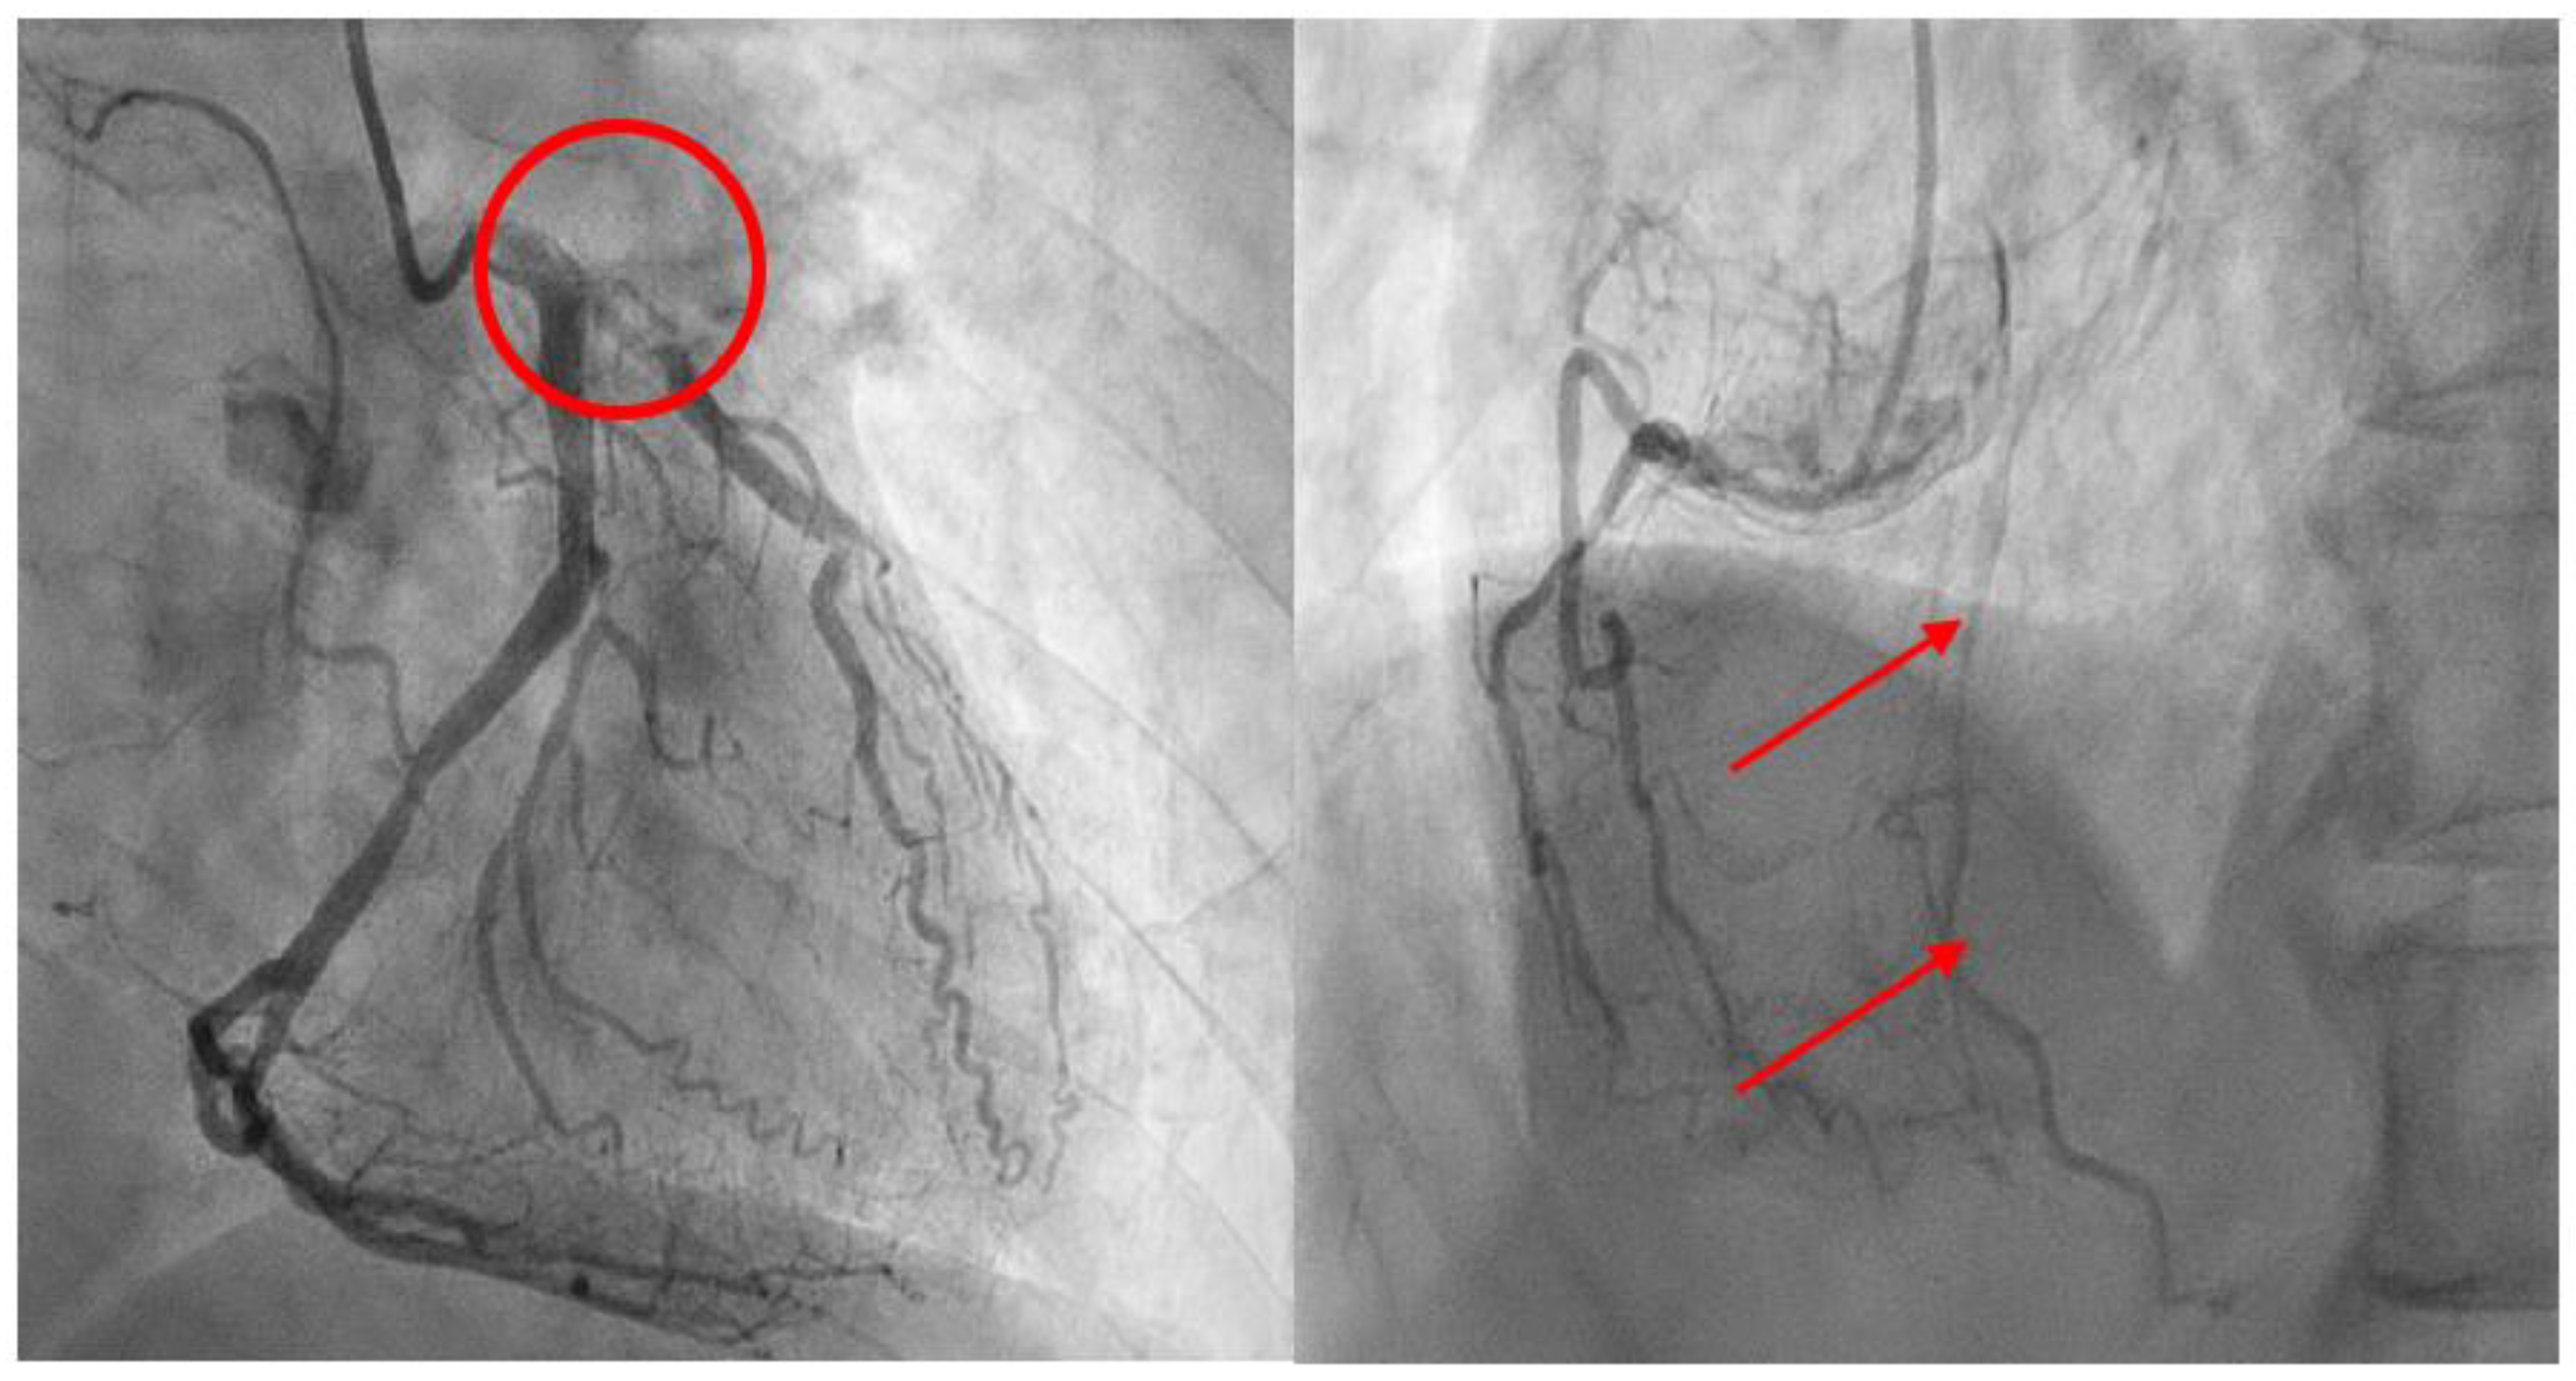

- Meier P, Schirmer SH, Lansky AJ, Timmis A, Pitt B, Seiler C. The collateral circulation of the heart. BMC Medicine. 2013;11:143. [CrossRef]

- Habib GB, Heibig J, Forman SA, Brown BG, Roberts R, Terrin ML, et al. Influence of coronary collateral vessels on myocardial infarct size in humans. Results of phase I thrombolysis in myocardial infarction (TIMI) trial. The TIMI Investigators. Circulation. 1991;83:739-46. [CrossRef]

- Pérez-Castellano N, García EJ, Abeytua M, Soriano J, Serrano JA, Elízaga J, et al. Influence of collateral circulation on in-hospital death from anterior acute myocardial infarction. J Am Coll Cardiol. 1998;31:512-8. [CrossRef]

- Saraon T, Chadow HL, Castillo R. The power of collateral circulation: a case of asymptomatic chronic total occlusion of the left main coronary artery. J Invasive Cardiol. 2012;24:E196-8.